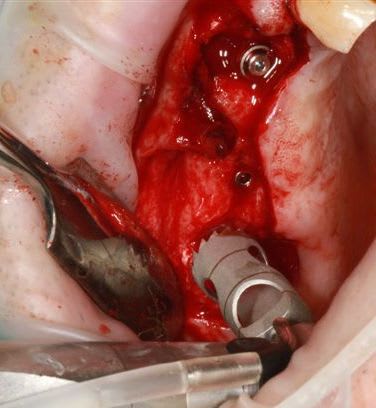

Ensuite zone 16 .. carottage, sciage en vest, carottage prélèvement de la carotte ajustage (délicat ça glisse:-)))

modelage zone 13,finitions, mise en place du bloc osseux, qui sera soigneusement impacté (pas de vis) prélèvement d'un petit bloc triangulaire pour finir la fermeture, éponges de gelatemp, sutures.

sur 2 ième et la troisième photo, tu utilises le disque pour pouvoir faire levier et sortir la carotte ?

Dans un premier temps oui, mais l'os etait trop "raide" donc j'ai repris la scie cloche en perpendiculaire.